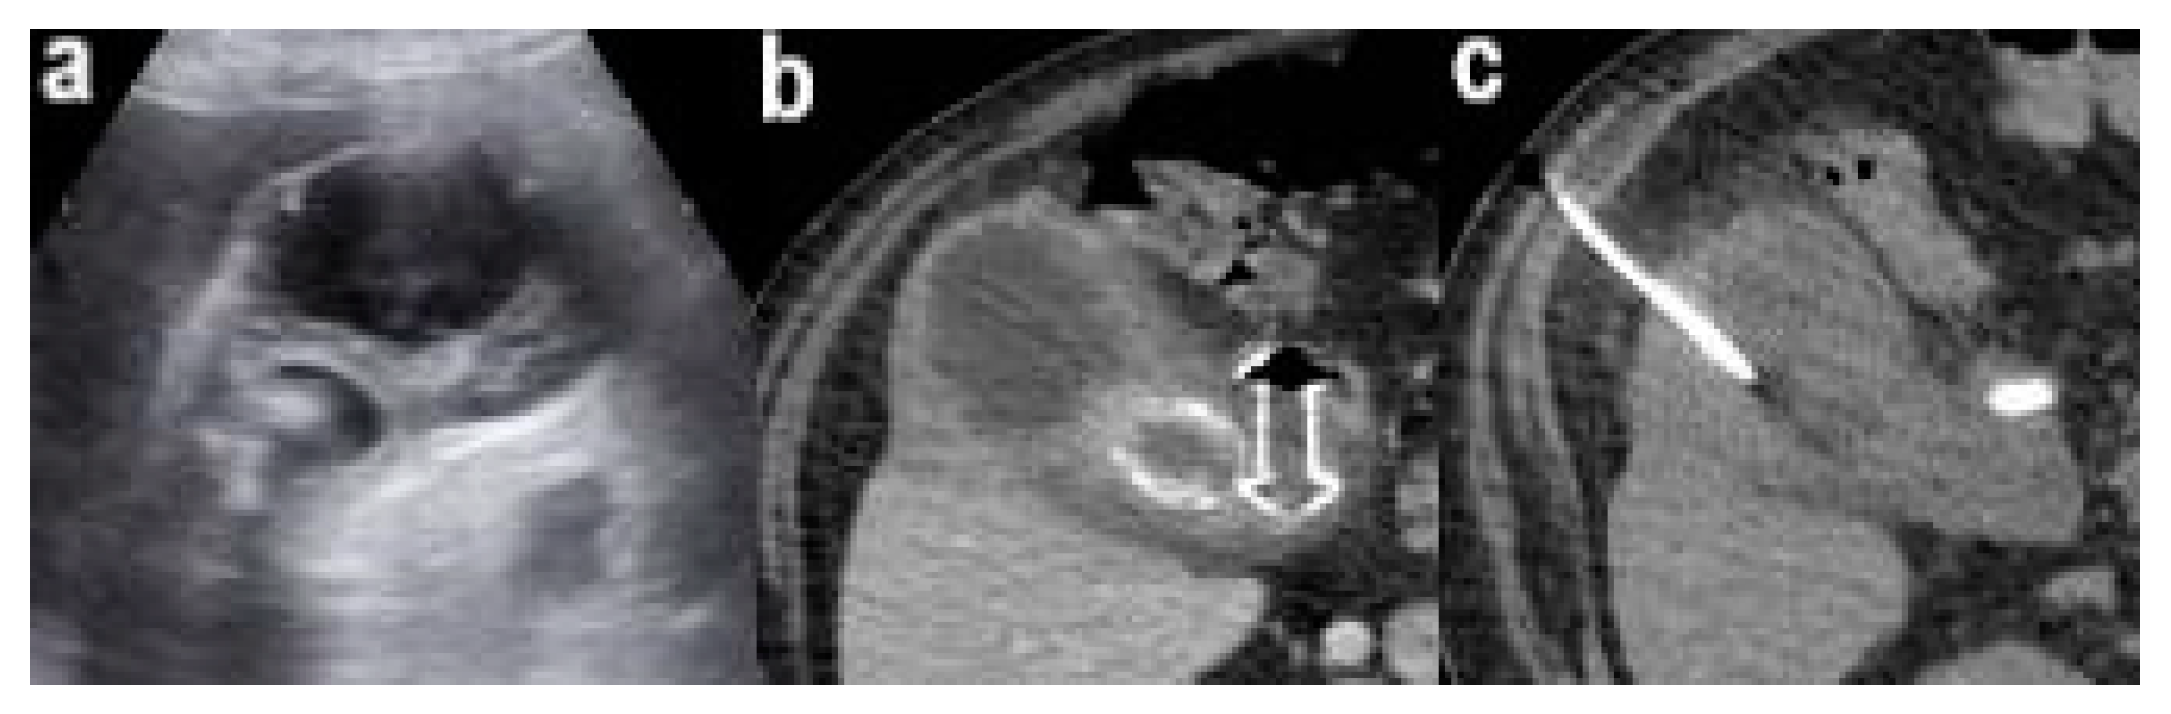

2. Case Report